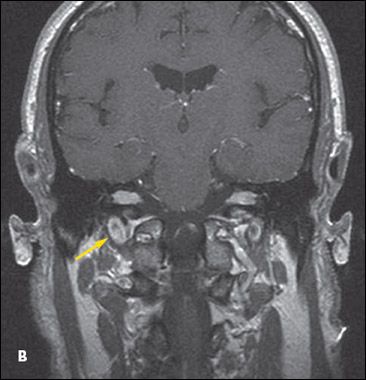

Findings on a CT scan of the head are unremarkable. MRI scans of the brain with gadolinium reveal enhancement along the meningeal surfaces of the right optic nerve and to a lesser degree of the left optic nerve (A), and expanded cranial nerves VII and VIII bilaterally (B). No evidence of hydrocephalus, intraparenchymal mass, or stroke is present.